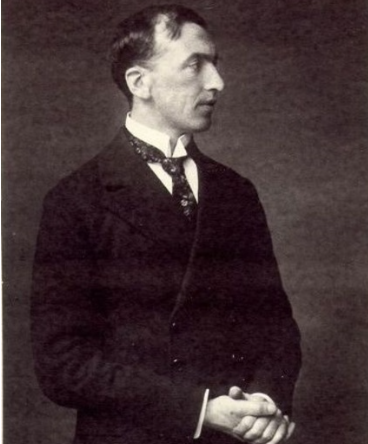

В начале 20-х годов ХХ века, когда во Франции шли исследования скрепи, немецкий врач Альфонс Мария Якоб описал пять случаев необычного заболевания человека, отличавшегося своеобразными клиническими симптомами и необычными изменениями в ЦНС у людей в возрасте от тридцати до пятидесяти лет. Обнаруживаемые у пациентов изменения были сходны только с изменениями, описанными ранее Гансом Герхардом Кройтцфельдтом, обнаруженными им при исследовании тела двадцатилетней девушки по имени Берта Е. Несчастная Берта при жизни страдала расстройствами зрения, навязчивыми мыслями об одержимости, нарушением координации движений и эпилептическими припадками. Учитывая эти обстоятельства, было принято решение назвать новое заболевание болезнью Кройтцфельдта-Якоба. Справедливости ради стоит сказать, что изменения, которые обнаружили Кройтцфельдт и Якоб, уже были известны учёным.

В начале марта 1957 года в изучение куру включился американский вирусолог словако-венгерского происхождения Карлтон Гайдушек. После этого началось интенсивное и плодотворное исследование неизвестной ранее болезни. Гайдушек был педиатром по образованию и вирусологом по призванию.